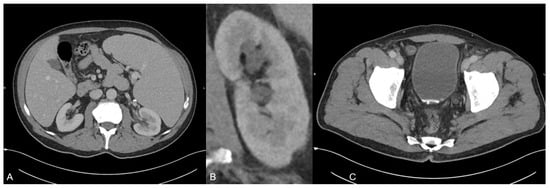

In order to further analyze the urine sedimentation, dual-energy CT-based material decomposition originally developed for kidney stone analysis differentiating uric acid from calcium was applied [10,11]. In this context, soft tissue kernel reconstructions of the 90 and 150 kV scan were fused, and dedicated postprocessing software (syngo.via, version VB10B, Siemens Healthineers) was used to generate dedicated coloured reconstructions using default settings. By application of this algorithm, it was possible to identify the red coloured uric acid in the hyperdense material (blue colour shows calcium) (A) by placing a circular region of interest in the hyperdense material. Furthermore, the software displayed the dual-energy ratio of the region of interest in a diagram indicating its uric acid content (B). Subsequently, the urologists stared a therapy including alkalinisation of the urine with potassium sodium hydrogen citrate based on the results of this dual-energy CT-based material analysis.